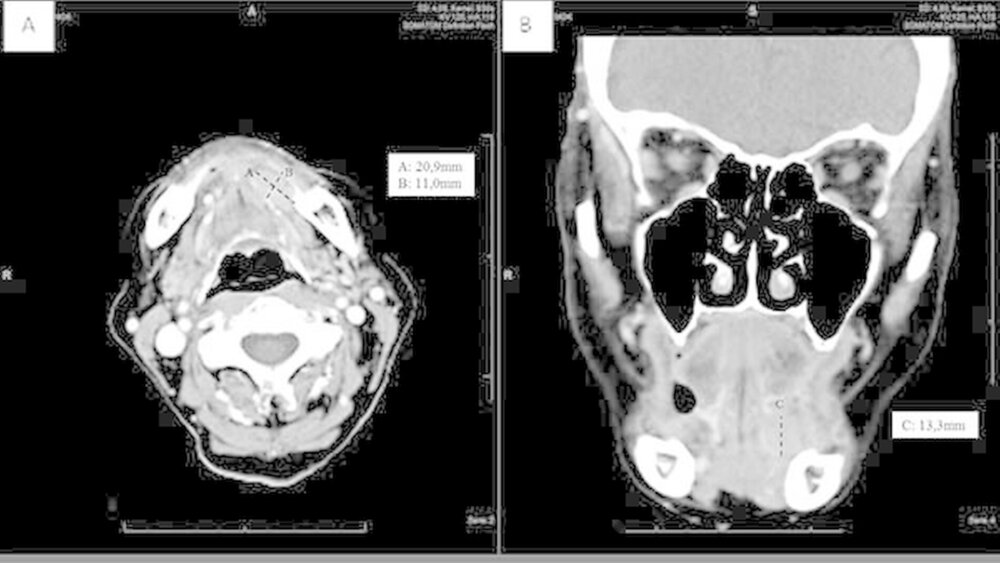

Bei der Antikörperbestimmung waren lediglich die ANA mit 1:360 (Norm < 1:80) erhöht. Im CT zeigte sich die Glandula sublingualis links glatt begrenzt und homogen kontrastmittelanreichernd mit einer Gesamtgröße von ca. 2,1 x 1,1 x 1,4 cm (Abbildungen 1a, b).